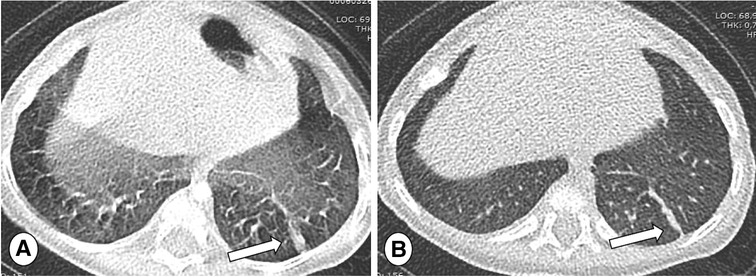

FIGURE 2

www.frontiersin.org

Figure 2. Posterior/anterior chest radiographs in (A) mild and (B) severe cystic fibrosis lung disease. Note the progressive increase of bronchial pathology in the subject with severe disease (B, arrows). The more severe the disease, the more difficult the detection of new abnormalities, especially during respiratory tract exacerbation.

FIGURE 3

Figure 3. Posterior-Anterior (PA) chest radiograph in mild (A) and severe (B) cystic fibrosis lung disease during respiratory tract exacerbation. Note large consolidation in the right lung base in image A indicating respiratory tract exacerbation (thick arrow) and bilateral consolidations in the right upper lobe and left lung base (B, thin arrows).